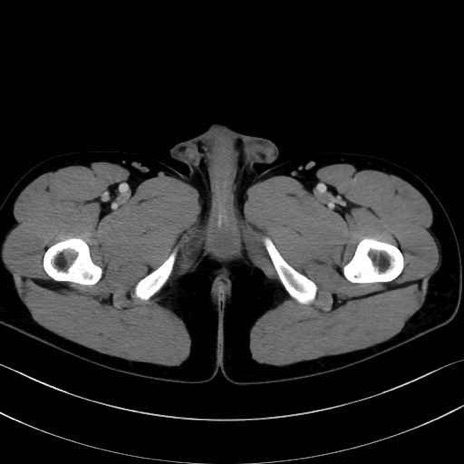

梨状筋(piriformis muscle) のCT画像の解剖

大腿方形筋 (Quadratus femoris)

恥骨筋 (Pectineus)

長内転筋 (Adductor longus)